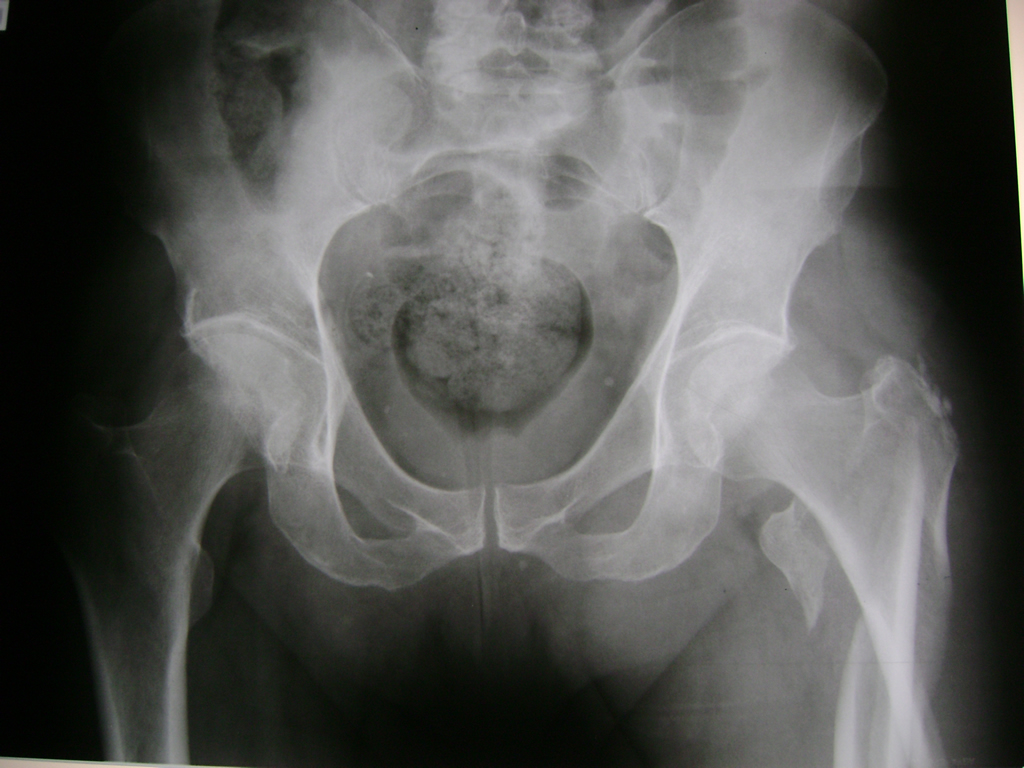

La cirugía de fractura de cadera se realiza para reparar una ruptura en la parte superior del hueso del muslo. Este hueso se denomina fémur.

Es parte de la articulación coxofemoral. Si una fractura de cadera no recibe tratamiento, es posible que deba permanecer en una silla o en la cama.